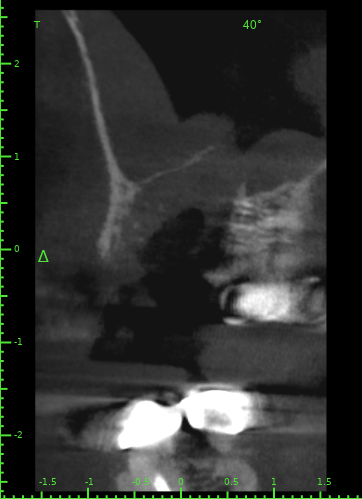

Atcotr Опубликовано 18 июля, 2024 Автор Поделиться Опубликовано 18 июля, 2024 @Женька @red_butler КТ сделано на 17-й день после удаления зуба. Не могли бы вы его посмотреть? Есть ли по вашему мнению свищ или признаки его формирования? Есть ли угроза для 27го импланта? Слизистая в гайморовой пазухе была опухшая задолго до удаления, это не новый процесс. КТ находится по ссылке: https://1drv.ms/f/s!AptB3I-32KWekuk4OkRq7Q6cdU7XcA?e=v69OYx Беспокоит чувство заложенности носа и уха слева после приёма любых жидкостей. Лечащий врач сказал, что небольшие перфорации в 95% случаев зарастают самостоятельно, назначил антибиотик и псевдоэфедрин и следующий приём через месяц. Спасибо за помощь. Ссылка на комментарий

Женька Опубликовано 19 июля, 2024 Поделиться Опубликовано 19 июля, 2024 Материала я, конечно, тут не особо вижу. Возможно он был, но весь вымылся. Перфорация действительно есть. Я бы ждал сейчас заживления и после оценивал формирование сообщения с пазухой. Снимок всю пазуху не вмещает, что там выше возле соустья неизвестно. Ухо, от ситуации на снимке, болеть вряд ли может на мой взгляд. Ссылка на комментарий